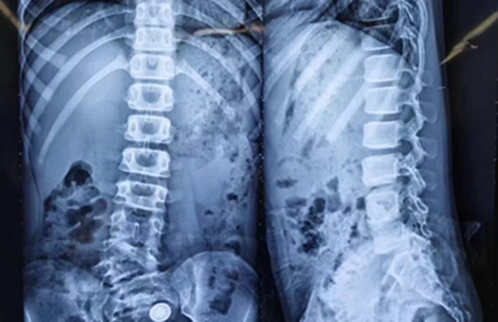

9 岁的女孩小怡(化名)因为先天性的腰半椎体畸形导致严重的脊柱侧弯,侧弯角度达到 50 度。刘主任带领团队评估后决定为她进行一场「高难度挑战」脊柱矫形手术。

术中,在弯曲最严重的位置精准截骨,将钛合金钉棒稳稳地固定在她的脊柱上用以扶正脊柱,并植入截骨后的骨粒以促融合。

小怡的脊柱「挺」直了。